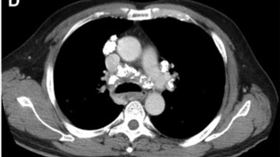

他胸悶檢查見鵝蛋大腫塊 醫:5症狀是警訊

一名60歲男性長期胸悶、呼吸不順,就醫檢查發現,一顆...